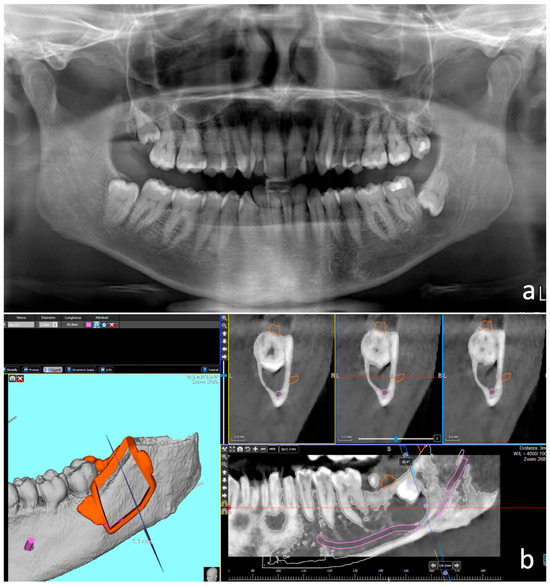

Computer-Guided Bone Lid Technique for Surgical Extraction。Advanced Material Strategy for Restoring Damaged。Predictive factors in the retrieval of endodontic。⚜️Ninja endodontic cavities and conservative endodontic。裁断済みのため状態は悪いにしています「How to Endodontics The State of the Art : ビジュアライズドイラストレーションズ」寺内 吉継定価: ¥ 13600#寺内吉継 #寺内_吉継 #本 #自然/医療・薬学・健康。